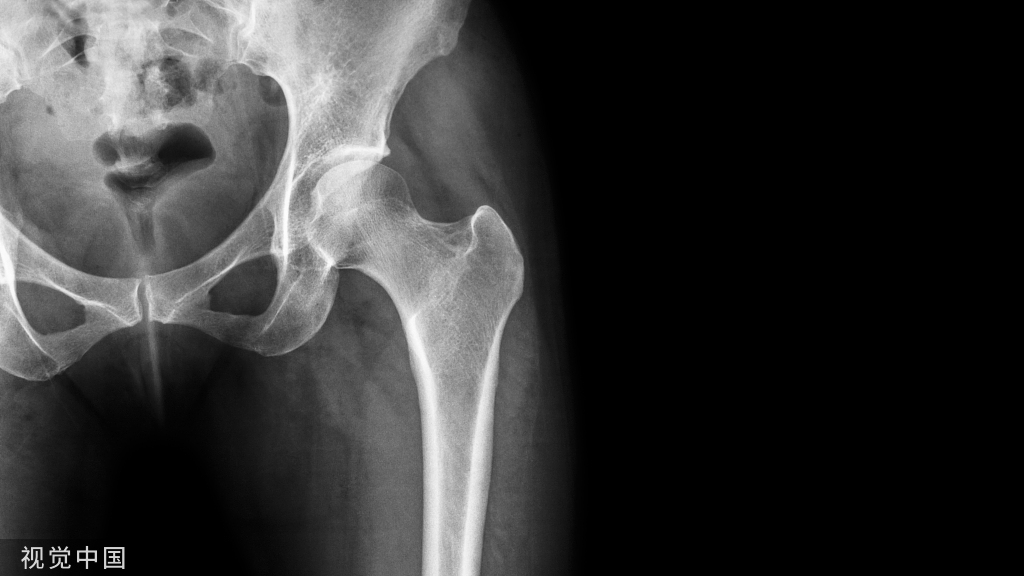

还有一些情况下术中使用双氧水,所利用的效应主要是止血而非抗菌消炎,主要用于大创面,比如髋关节返修手术和大创面肉芽清理后的止血、植皮。机理是使小血管在强氧化烧灼下,蛋白变性自动止血,相当于上万个电刀作用。